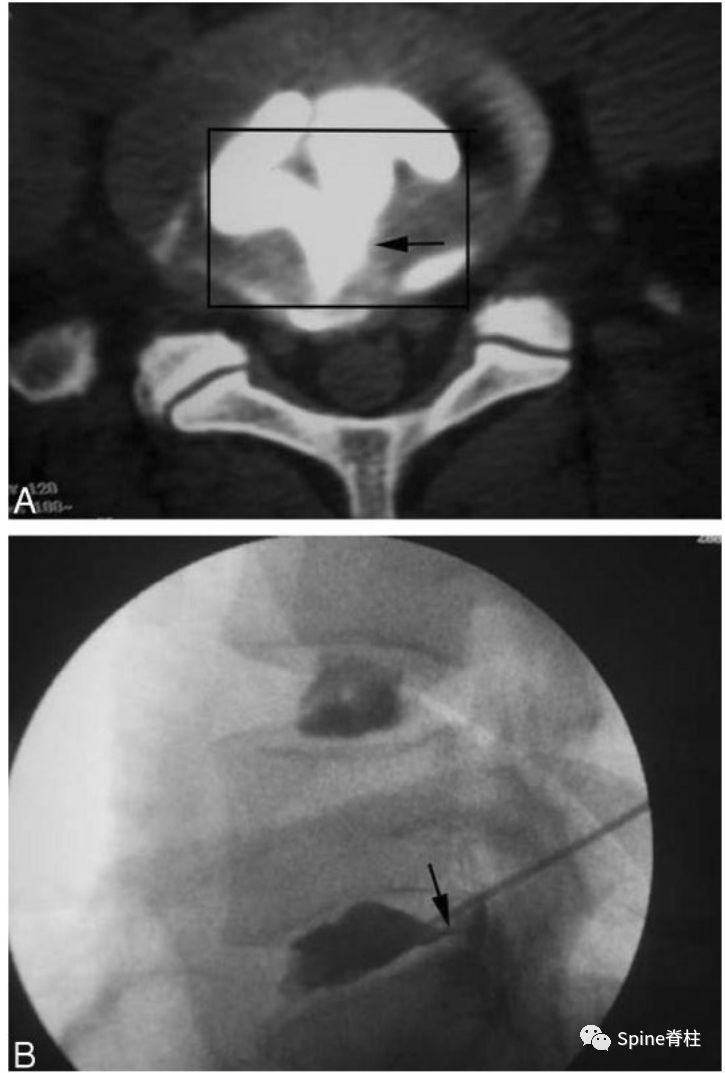

“黑椎间盘”是不是疼痛的?通常需要椎间盘造影或阻滞来明确或排除。虽有争议,目前腰椎间盘造影术仍是诊断椎间盘源性腰痛的“金标准”。椎间盘造影诱发平时疼痛是明确疼痛椎间盘的有效方法,或者椎间盘内注射*醉药麻**(比如布比卡因)后平时的腰痛症状明显消失。疼痛的椎间盘在造影剂注射过程中,造影剂要么通过放射状纤维环撕裂流向椎间盘外方,要么通过放射状终板撕裂流向椎体,两者都诱发患者平时的腰痛反应。这也是鉴别终板源性腰痛和由纤维环撕裂引起的椎间盘源性腰痛的主要手段。

图:椎间盘造影时,造影剂流至椎管

图:椎间盘造影时,造影剂流至破损的终板